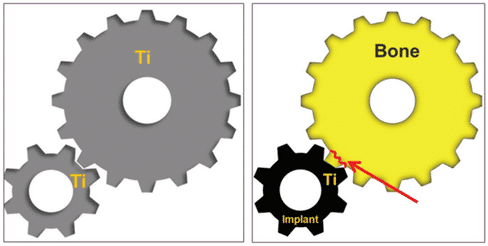

(Figure 8) Causes des micro-fractures.

Parmi les diverses causes d’échec des procédures d’implantation dentaire, l’une d’entre elles est la micro-fracture entre l’os alvéolaire et l’implant. Les micro-fractures peuvent être dues à différents facteurs, et le Magic Fin Thread du MagiCore a été spécialement développé pour répondre à la possibilité de micro-fractures causées par les propriétés physiques différentes du titane, utilisé pour l’implant, et de l’os alvéolaire (figure 8).

Lorsqu’un patient est restauré avec un implant pour remplacer une dent manquante, les forces occlusales sont transmises à l’os alvéolaire à travers la structure de l’implant. En d’autres termes, la force est transférée à la zone de contact direct entre l’implant et l’os alvéolaire. Cependant, le titane ou les alliages de titane couramment utilisés pour fabriquer les implants ont des propriétés physiques différentes de celles de l’os alvéolaire, ce qui augmente le risque de micro-fractures.

MagiCore a pris cela en compte et a été développé pour avoir des propriétés physiques aussi proches que possible de celles de l’os alvéolaire, réduisant ainsi la probabilité de micro-fractures.